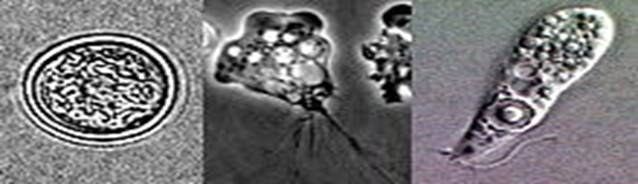

Chu kỳ sinh học với các giai đoạn nang, roi và tư dưỡng (Cyst, Flagellate, Trophozoite).

Naegleria fowleri tồn tại trong 3 thể: thể nang, tư dưỡng (ameboid) và roi (flagellate).

Chu kỳ của amip N. fowleri và các amoebae sống tự do (theo hình ảnh trên)